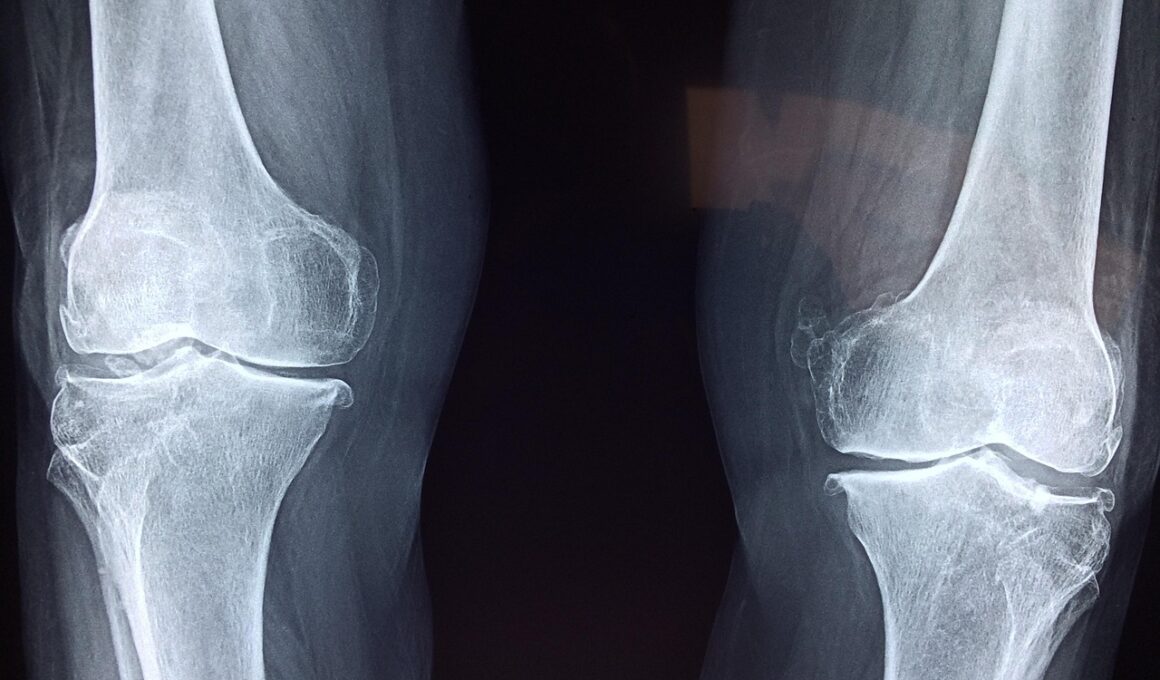

Finally, educating yourself about knee injuries and their risks is instrumental in injury prevention. Players should become knowledgeable about the common symptoms associated with knee injuries. Recognizing signs such as pain, swelling, or stiffness can prompt early interventions that prevent further damage. Understanding the mechanics of your body can also influence how you play and move on the court. Sessions with a certified coach can provide insights on your technique, allowing you to identify areas that may lead to improper movements. Additionally, participating in workshops on injury prevention can arm players with the right strategies to safeguard against knee injuries. Engaging with a community or support network of players can also create a more informed environment that promotes health and safety. Injuries can be daunting, but being proactive in your education and adopting best practices can greatly enhance your ability to enjoy the game safely. By understanding and employing these preventative measures, tennis players can ensure a smoother, injury-free experience on the court.